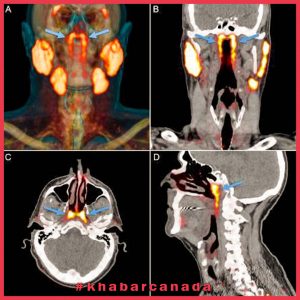

به گزارش خبرکانادا و به نقل از لایو ساینس دانشمندان مجموعهای از غدد بزاقی را کشف کردند که در اعماق قسمت فوقانی گلو قرار دارند

طول مجموعههای تازه کشف شده به طور متوسط حدود 1.5 اینچ (3.9 سانتی متر) است. کاشفان این غدد جدید به دلیل قرار گرفتن در بالای یک غضروف به نام torus tubarius ، آنها را غدد بزاقی توباری لقب دادهاند. این غدد احتمالاً قسمت فوقانی حلق پشت بینی و دهان را مرطوب میکنند. طبق مقالهای که محققان در 23 سپتامبر در مجله Radiotherapy منتشر کردهاند،

این کشف به طور تصادفی شکل گرفت و محققان سرطان در هلند از ترکیبی از سی تی اسکن و توموگرافی انتشار پوزیترون (PET) به نام PSMA PET-CT برای مطالعه سرطان پروستات استفاده کردند. در اسکن PSMA PET-CT ، پزشکان یک “ردیاب” رادیواکتیو به بیمار تزریق می کنند. این ردیاب به خوبی به پروتئین PSMA متصل می شود که در سلولهای سرطانی پروستات افزایش یافته است. آزمایشات بالینی نشان داده است که اسکن PSMA PET-CT در تشخیص سرطان پروستات متاستاز شده بهتر از تصویربرداری معمولی است.